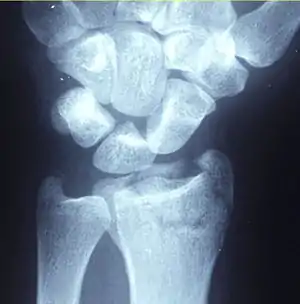

Diagnosis may be evident clinically when the distal radius is deformed, but should be confirmed by X-ray. The differential diagnosis includes scaphoid fractures and wrist dislocations, which can also co-exist with a distal radius fracture. Occasionally, fractures may not be seen on X-rays immediately after the injury. Delayed X-rays, X-ray computed tomography (CT scan), or Magnetic resonance imaging (MRI) can confirm the diagnosis.

X-ray of the affected wrist is required if a fracture is suspected. Posteroanterior, lateral, and oblique views can be used together to describe the fracture.[5] X-ray of the uninjured wrist should also be taken to determine if any normal anatomic variations exist before surgery.[5]